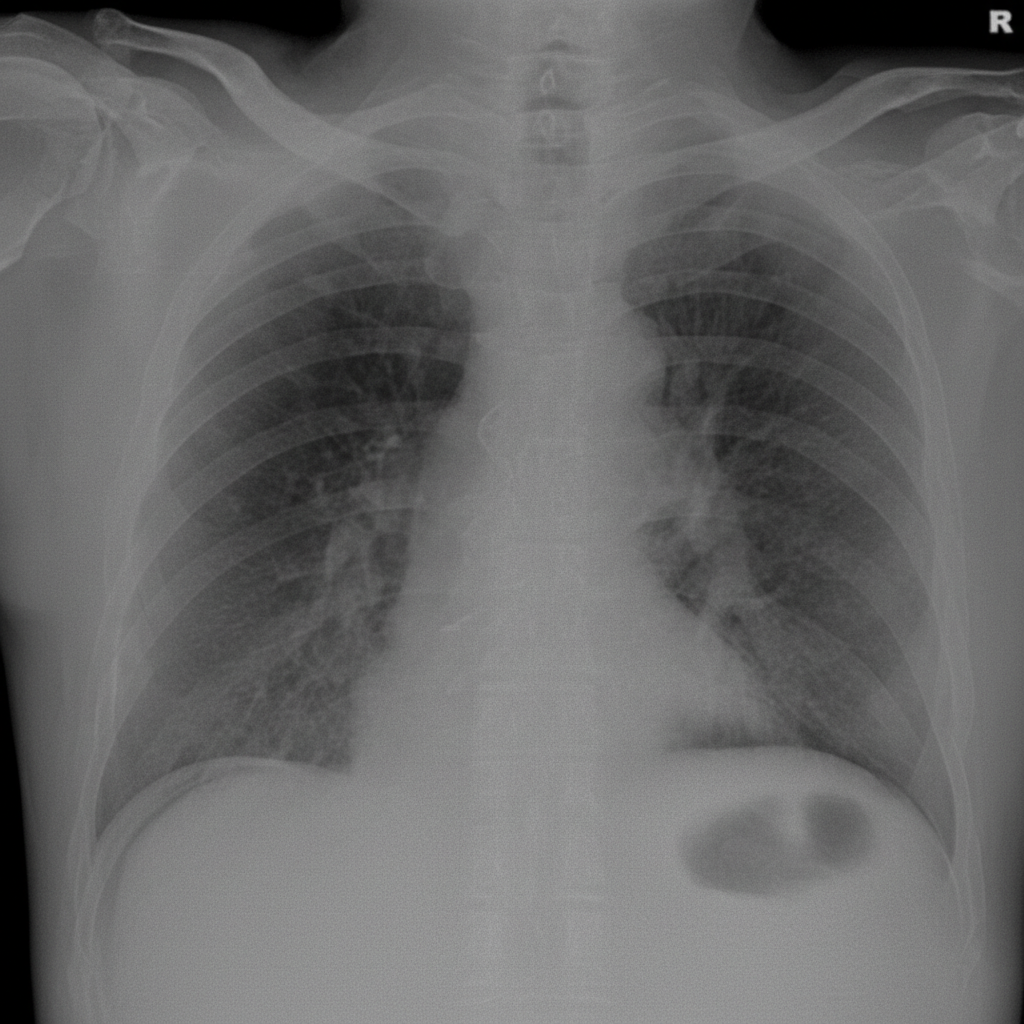

A 56-year-old man is brought to the emergency department after 4 hours of severe abdominal pain with an increase in its intensity over the last hour. His personal history is relevant for peptic ulcer disease and H. pylori infection that is being treated with clarithromycin triple therapy. Upon admission his vital signs are as follows: pulse of 120/min, a respiratory rate of 20/min, body temperature of 39°C (102.2°F), and blood pressure of 90/50 mm Hg. Physical examination reveals significant tenderness over the abdomen. A chest radiograph taken when the patient was standing erect is shown. Which of the following is the next best step in the management of this patient?